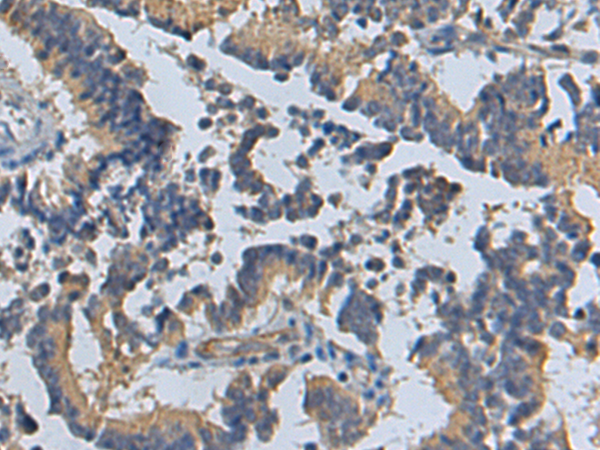

分类: 科研抗体货号: P04759别名: 1F5; EJ16; EJ30; EL32; G344; MIN1; MIN2; MIN3; MIRL; HRF20; MACIF; MEM43; MIC11; MSK21; 16.3A5; HRF-20; MAC-IP; p18-20应用: WB,IHC反应种属: Human